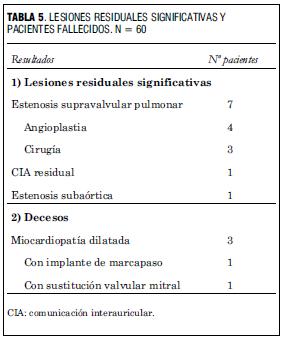

Las lesiones residuales significativas se presentaron en nueve pacientes (15%). Siete pacientes con estenosis supravalvular pulmonar, uno de ellos asociada a estenosis del origen de la arteria pulmonar rama izquierda, que requirieron angioplastia con balón (figuras 6 y 7), siendo efectiva en cuatro, mientras que en los otros tres requirió cirugía reparadora con la colocación de parche de pericardio bovino. Un paciente presentó una comunicación interauricular residual que debió ser cerrada quirúrgicamente, y otro paciente desarrolló una estenosis subaórtica (figura 8) que se resecó quirúrgicamente, todos con buena evolución (tabla 5).

Tres pacientes (5%) fallecieron por miocardiopatía dilatada, uno presentó bloqueo aurículoventricular (AV) de segundo grado que requirió la colocación de marcapaso y en otro se efectuó sustitución de la válvula mitral. En ninguno de los casos se obtuvo la autorización de estudio necrópsico para determinar la anatomía y las lesiones del árbol coronario.